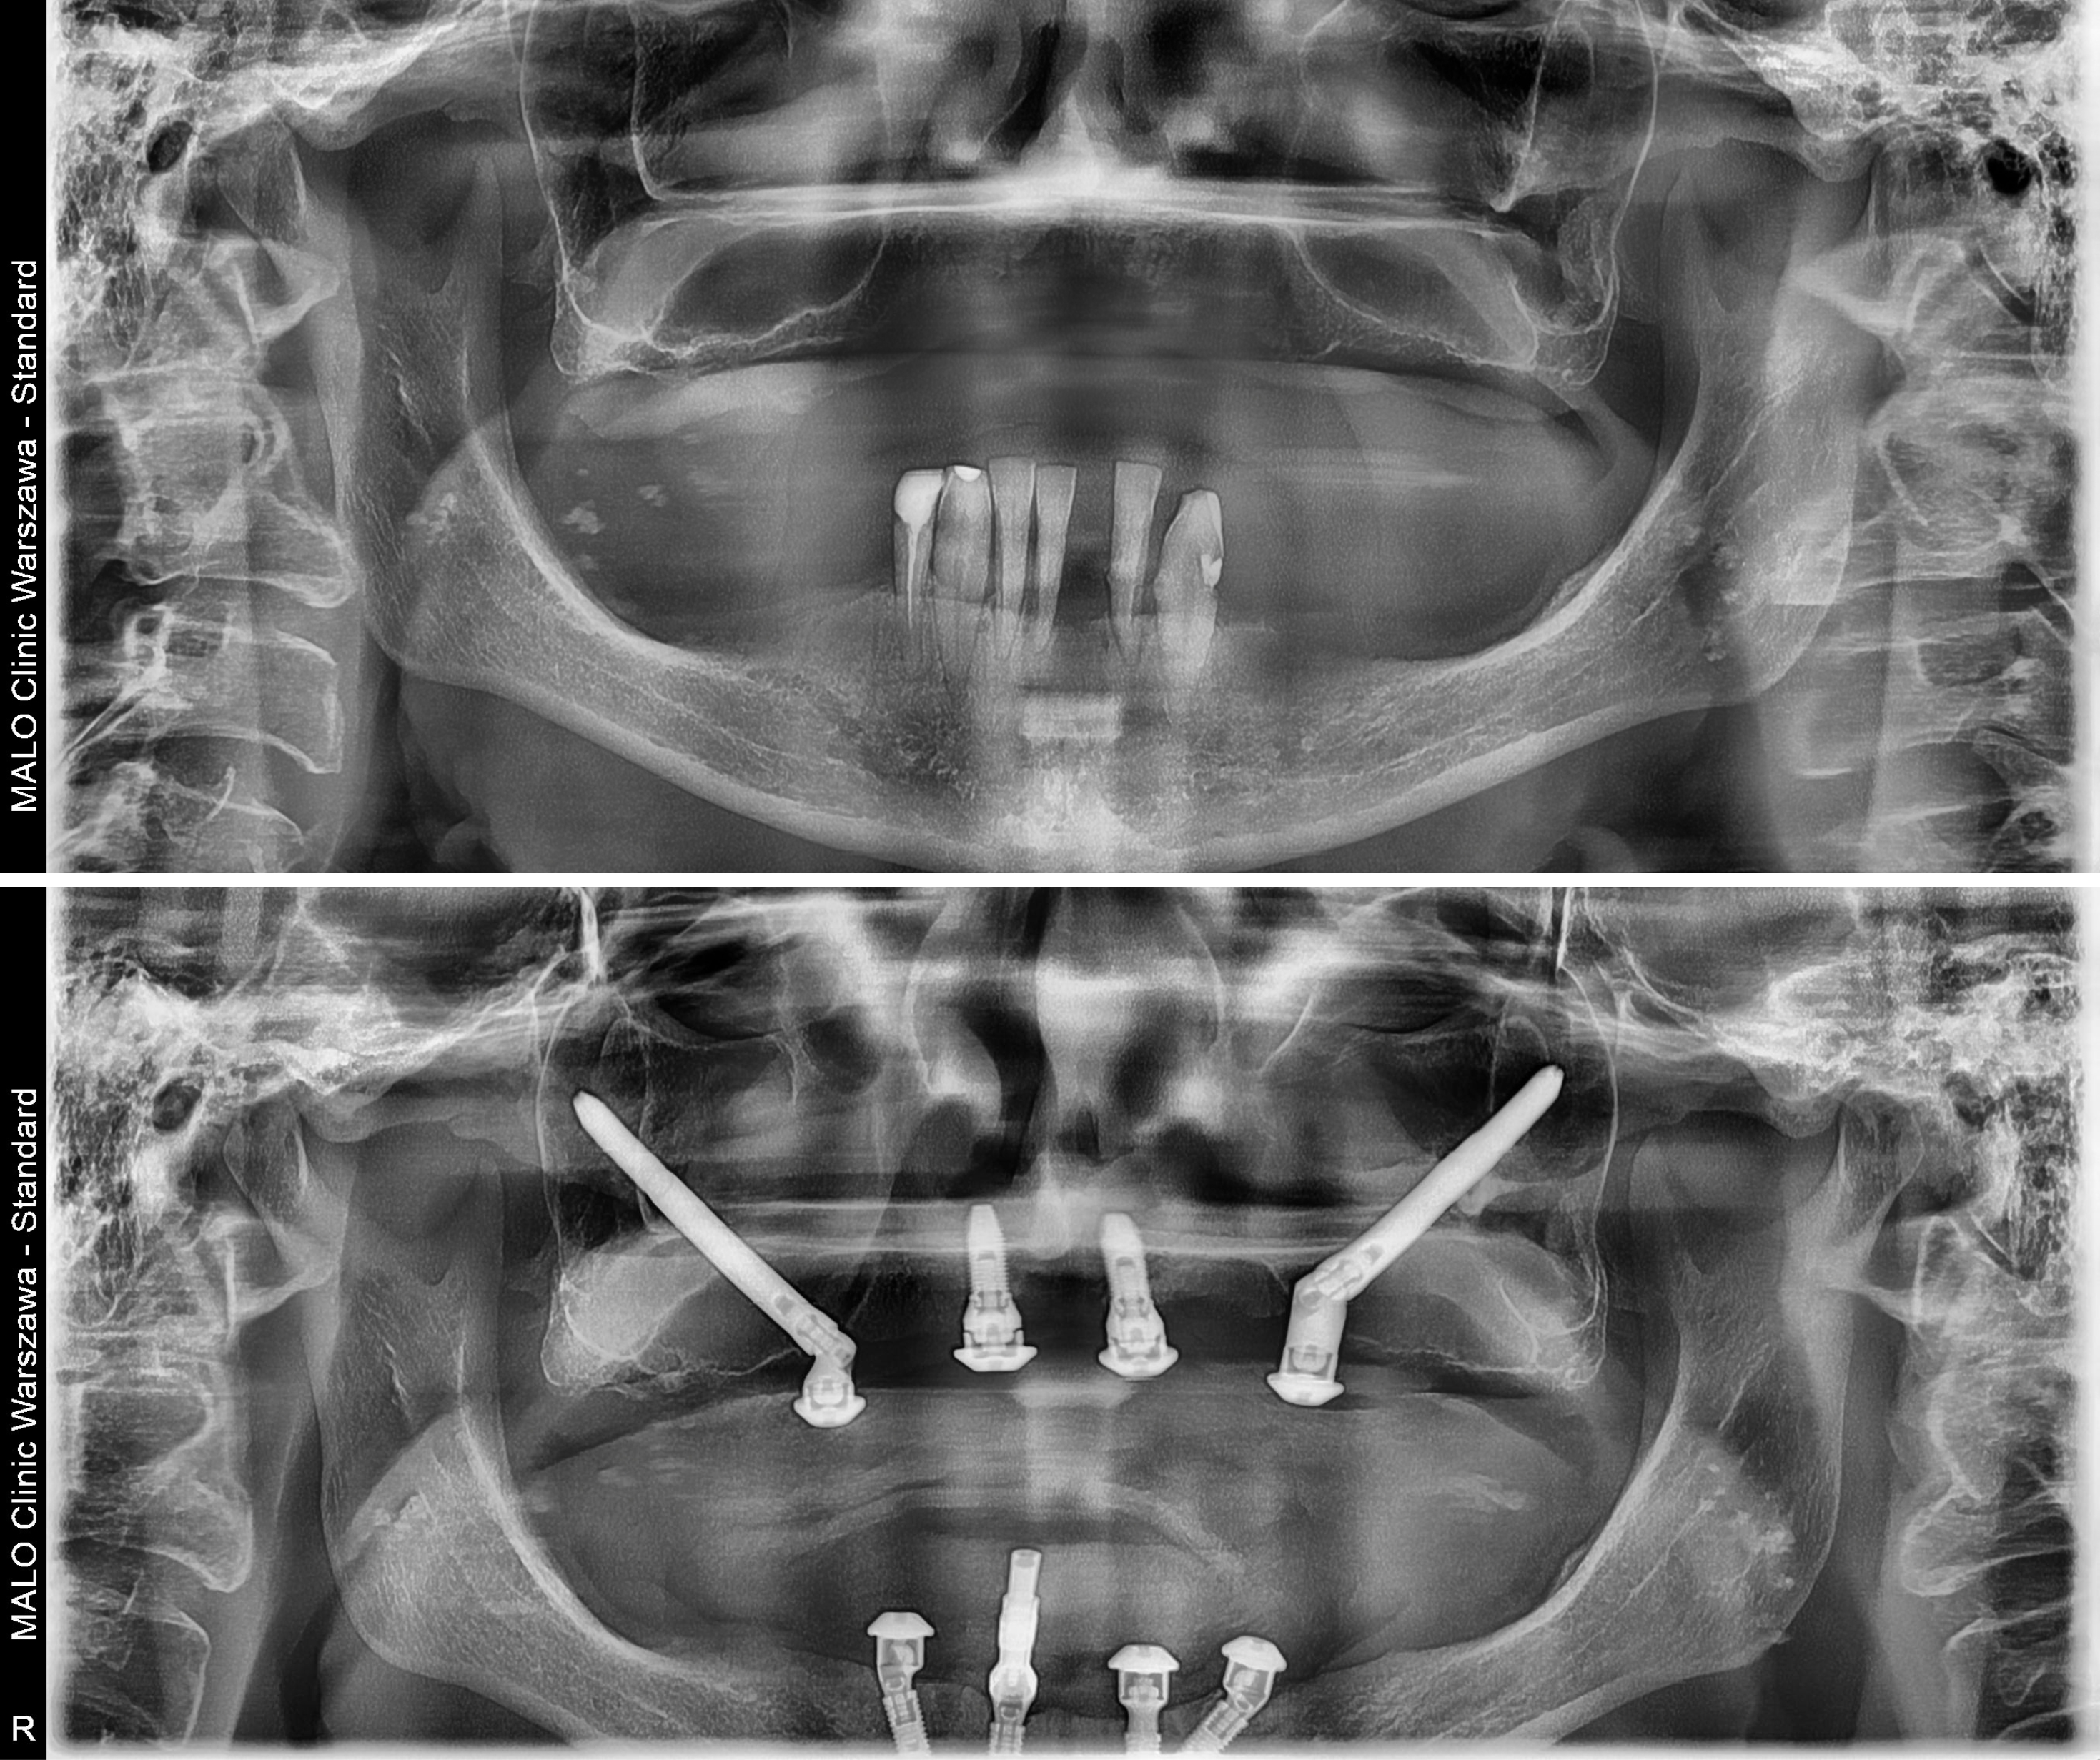

Po wykonaniu pełnej diagnostyki, obejmującej:

- badanie stomatologiczne i ocenę jamy ustnej,

- zdjęcie panoramiczne (OPG),

- tomografię komputerową,

- analizę stanu zdrowia ogólnego,

zespół specjalistów zakwalifikował Panią Jadwigę do zabiegu Malo Clinic Protocol – w stopniu Hybrid (połączenie implantów klasycznych i zygomatycznych) w szczęce oraz High Skill w żuchwie (cztery implanty klasyczne w miejscach o największej gęstości kości).

Dzięki nowoczesnej technologii i doświadczeniu zespołu udało się uniknąć przeszczepu kości, mimo znacznego zaniku.

- Wszczepienie czterech implantów w górnym łuku (2 klasyczne z przodu i 2 zygomatyczne w kości jarzmowej),

- Wszczepienie czterech implantów klasycznych w żuchwie,